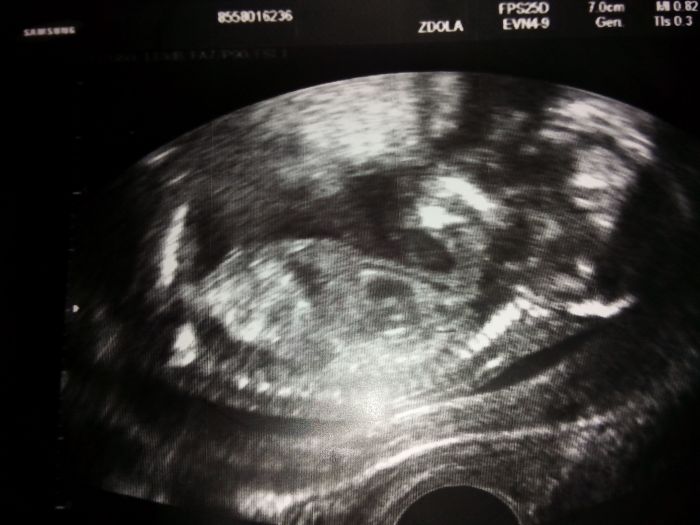

Dobré ráno děvčátka,no tak já mám foteček hodně, nechávám si vytisknout skoro pokaždé co jsem na kontrole :-)přikládám vám fotečky od teď až po mrňouska úplně na začátku těhu :-) založím je asi do alba potom, musím nějaké koupit